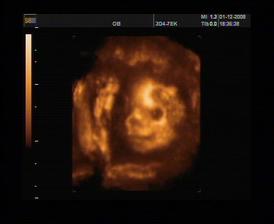

23.7.2008 první ultrazvuk - hurrrááá máme fotečku,